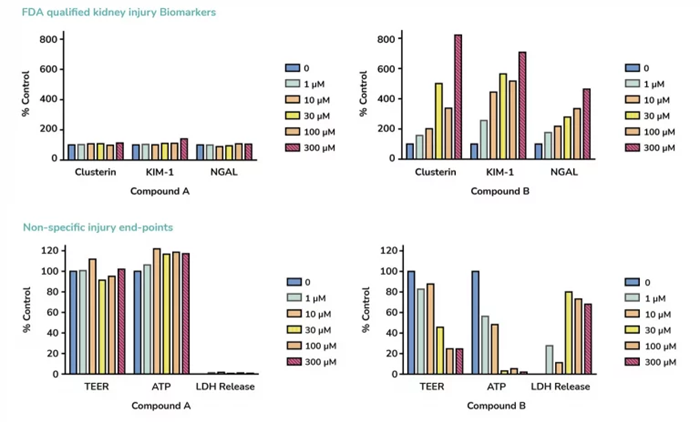

- Evaluation of KIM-1, NGAL, and clusterin, three FDA-approved biomarkers of kidney toxicity

- Cell viability: ATP, LDH, and TEER measurements

A high content comparison of two compounds for drug safety prediction using aProximateTM PTCs indicates a possible nephrotoxic effect for compound B with increased injury biomarkers and decreased non-specific injury endpoints. Compound A is predicted as non-toxic. Image Credit: Newcells Biotech

Evaluating FDA-approved biomarkers (KIM-1, NGAL, and clusterin) in the aProximateTM proximal tubule cell model is an example of a renal toxicity package. The monolayer integrity and drug-induced cell health can be evaluated using both kidney tissue models. Three distinct biological donor kidneys from various species can be used to obtain data.

- Assessment of FDA-approved biomarkers of renal toxicity: KIM-1, NGAL and clusterin (ELISA/MSD)

- Cell viability: ATP, LDH, and TEER measurements